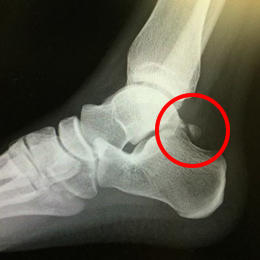

バレエダンサーや、サッカー選手は足関節を底屈(足首を伸ばす)することが多く、足首の後ろ側を痛める事が多く見られます。

足関節の距骨という骨の後ろ側が大きく突き出していたり、離れて過剰骨となっている人(三角骨といいます)が何度も足関節を底屈すると、その骨が脛骨と踵骨の間に挟まりこみ(インピンジメント)足関節の後方に炎症を起こし、痛みの原因となるのです。

![]() 三角骨(距骨の後ろ側の骨) |

![]() 足首を伸ばす(底屈する)ことで挟まりこむ |